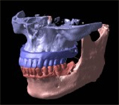

普通、歯科医院で撮影している「レントゲン写真パノラマ」というのがこのような写真です。

横面から撮影していますので、平面しか見ることはできません。

では、CTで撮影したものがどう見えるのかご覧下さい。

従来のインプラント手術ではパノラマレントゲンを参考にして手術をしますが

なんといってもそれは平面図ですので、立体的に把握することは不可能です。

当然間違いが起こります。